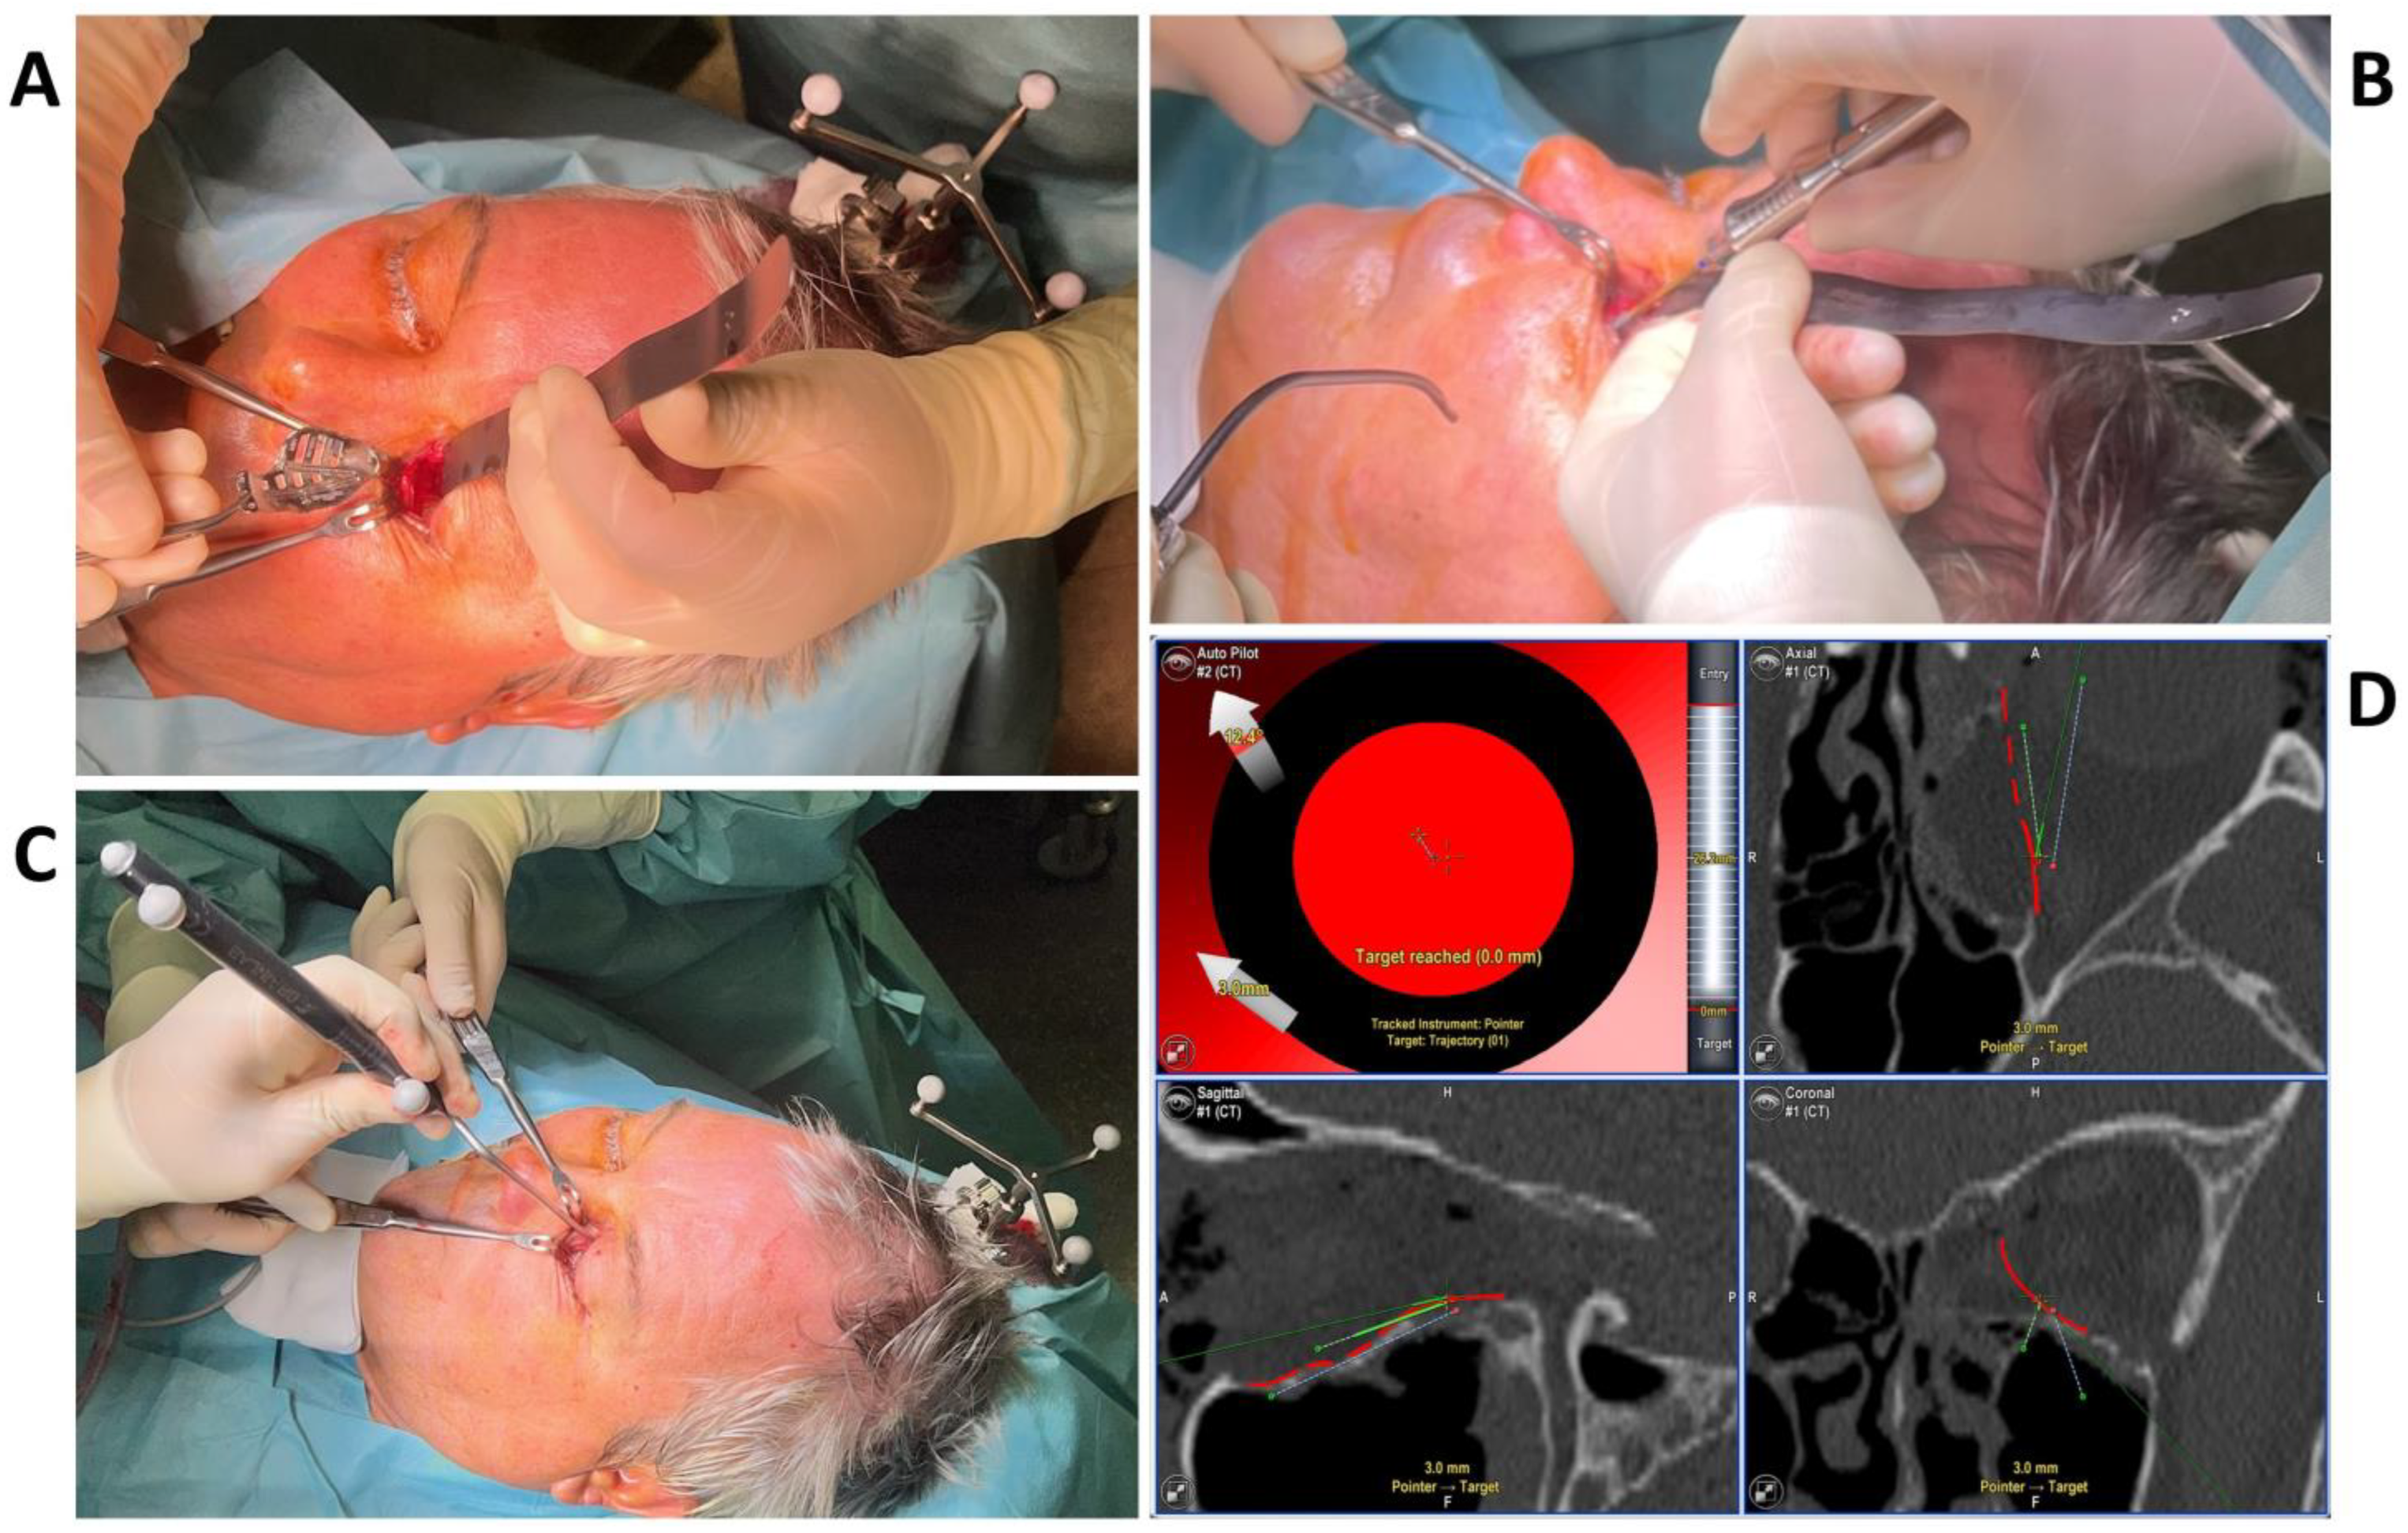

2. Methods and Results

2.2. Surgery